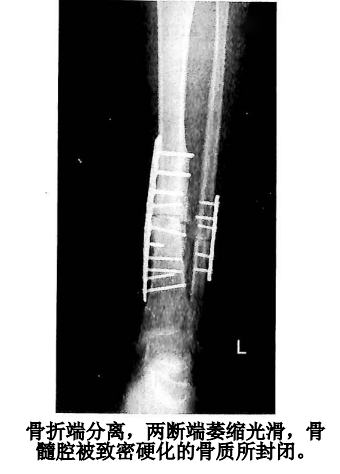

④萎缩性骨不连

骨折断端骨质疏松并萎缩,继发于中间骨块缺失或者无成骨能力的瘢痕组织嵌入骨折断端,明显的不稳定使原始骨皮质吸收、导致末端呈圆形。

主要继发于粉碎性的开放骨折或合并有严重的软组织创伤的骨折,但肱骨比较特殊,血供较好且初次手术的肱骨闭合骨折可能会出现萎缩型骨不连。